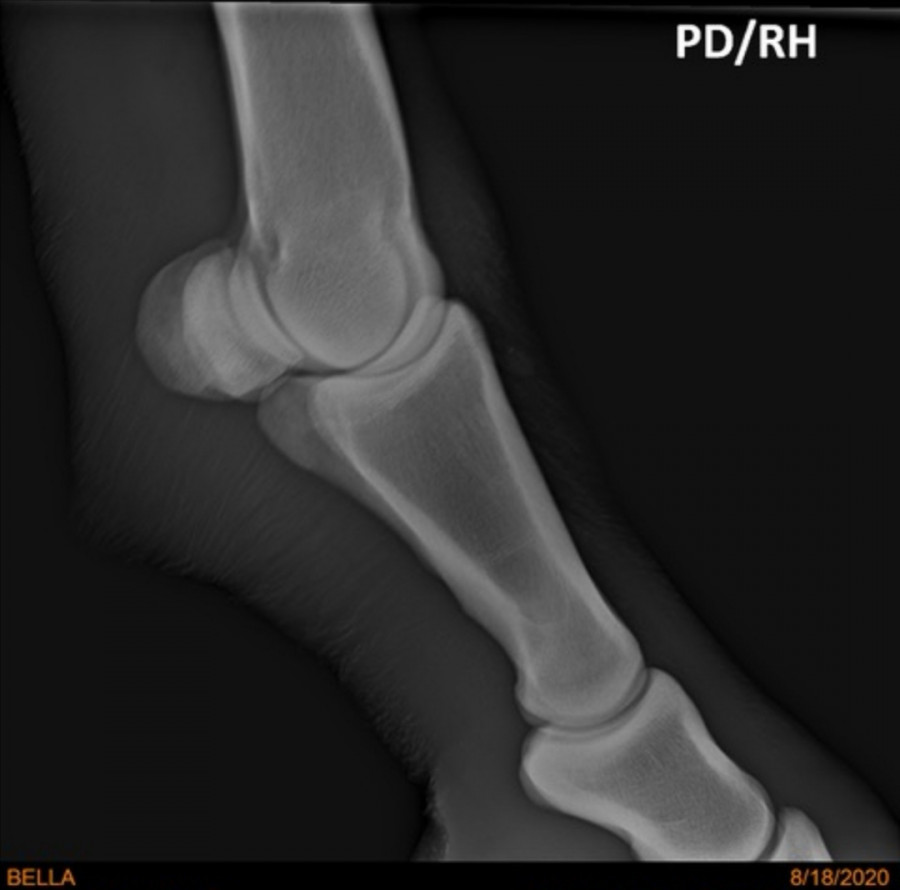

Je poste les radios qui avaient été faites quand même. La veto n'avait rien vu mais au cas où...